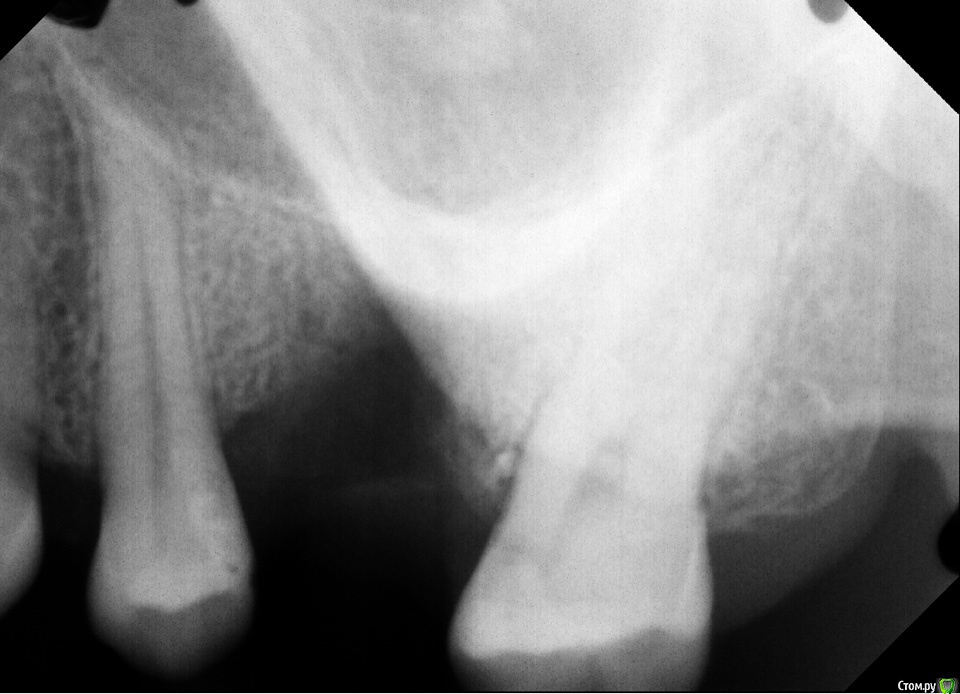

AlinaKh Опубликовано 18 декабря, 2016 Поделиться Опубликовано 18 декабря, 2016 (изменено) Добрый День! 05 декабря 2016 был установлен зубной имплант Нобель с проведением синус лифтинга.Прошло менее двух недель, десна болит при прикосновении, покраснела и немного опухла, образовался гнойный свищ. Я сейчас нахожусь не в России, сходила к врачу, сделали снимки, прописали антибиотики, ничего толкового не сказали, проконсультируйте, пожалуйста. Снимки в формате .RVG, не могу прикрепить, так как превышают допустимый размер загрузки, но могу выслать на почту или ссылка на скачивание: https://cloud.mail.ru/public/7SHB/6YQVVPEKm Спасибо, Алина. Изменено 18 декабря, 2016 пользователем AlinaKh Ссылка на комментарий

AlinaKh Опубликовано 18 декабря, 2016 Автор Поделиться Опубликовано 18 декабря, 2016 (изменено) Выкладывайте снимки в jpg форматеПрикрепила снимок , спасибо! Изменено 18 декабря, 2016 пользователем AlinaKh Ссылка на комментарий

AlinaKh Опубликовано 20 декабря, 2016 Автор Поделиться Опубликовано 20 декабря, 2016 Чтоб ответить на этот вопрос надо знать изначальную ситуацию, ваш анамнез и ход той операции. Для начала.Всем спасибо! Имплант был удалён, вот снимки до и после Ссылка на комментарий